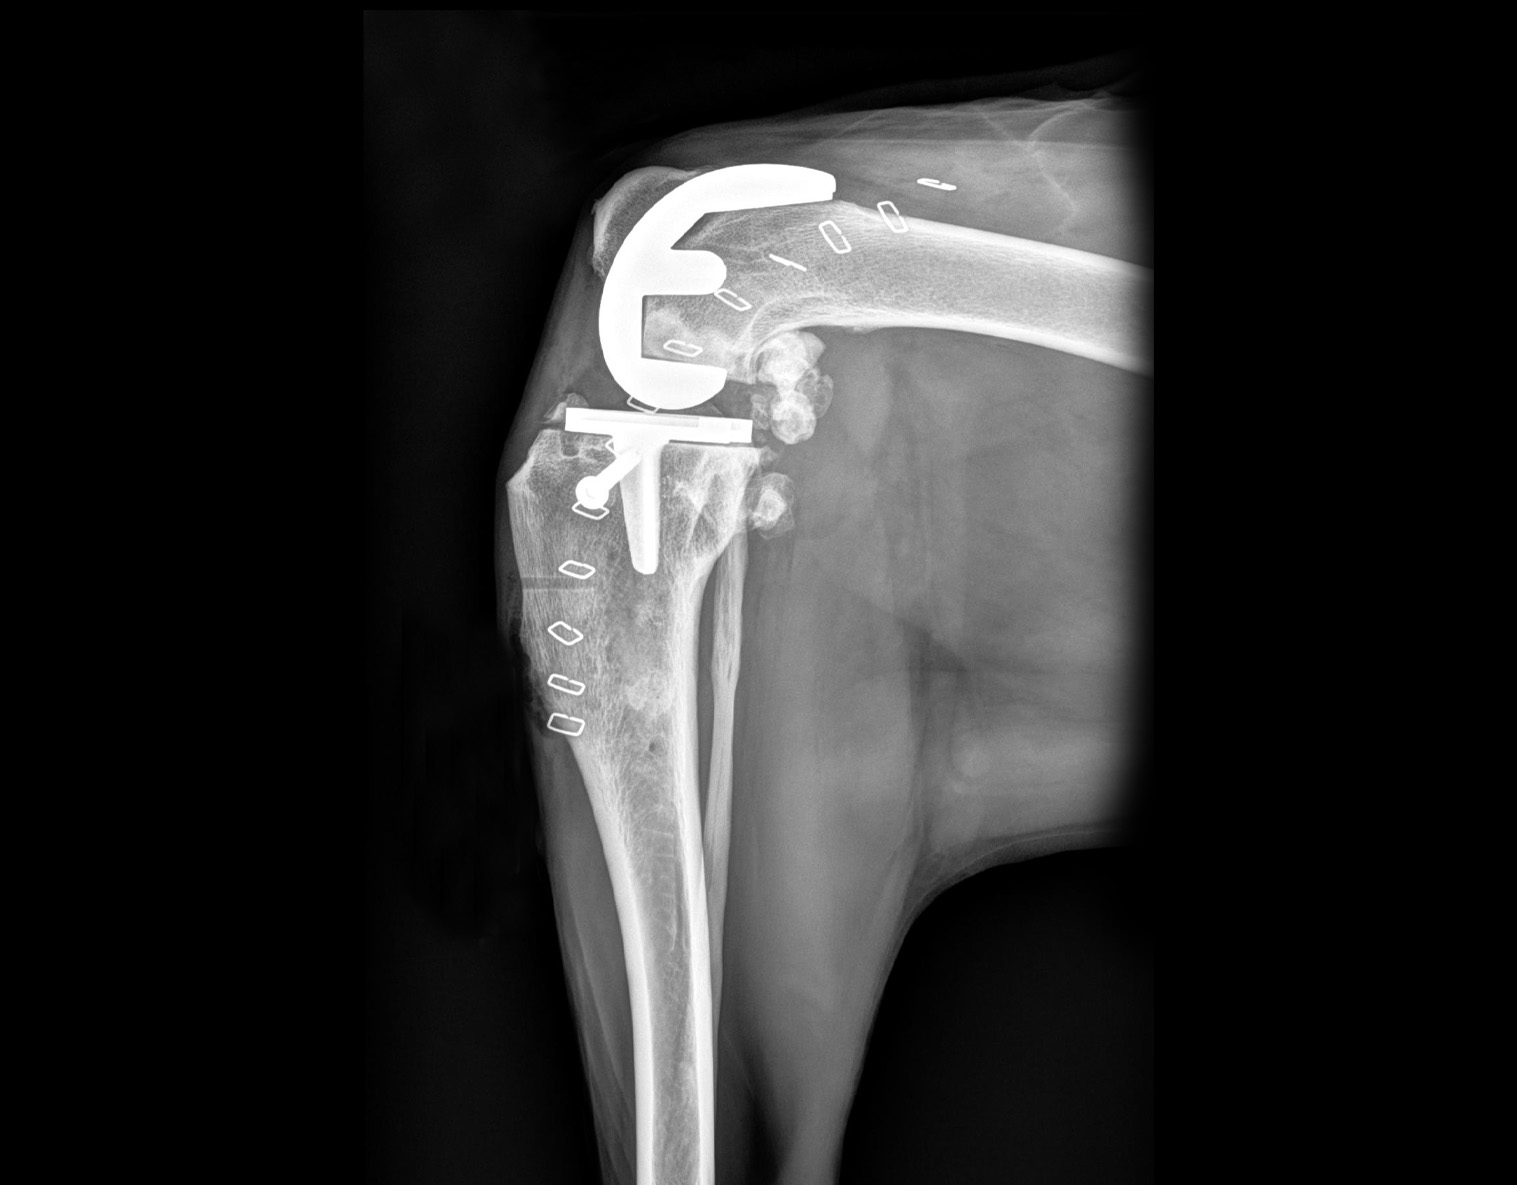

Dates of Surgery: November 16, 2021

Product: Canine Total Knee

Surgeon: Dr. Laurent Guiot; ACCESS Bone & Joint Center, Culver City, California

“Chelsea was very active in her youth, but by 9 years of age, had sustained multiple injuries, including a fracture to her right thoracic limb as well as bilateral TPLOs. It was clear her back right leg was her biggest challenge; it was atrophied, had little muscle definition, and arthritis in the knee had made it twice its size. Rather than treat with anti-inflammatories and pain medication, Chelsea’s owner decided on total knee replacement to address her pain and chronic lameness. She was taken to Dr. Guiot for a total knee replacement on her right knee. Chelsea’s owner reports that the difference in her mobility has been significant! After a matter of weeks, Chelsea was able to offload her chronic thoracic limb lameness and bear-weight on her surgery leg. Today she has her muscle tone back, is running after tennis balls, playing with other dogs, and jumping onto the couch all by herself!”